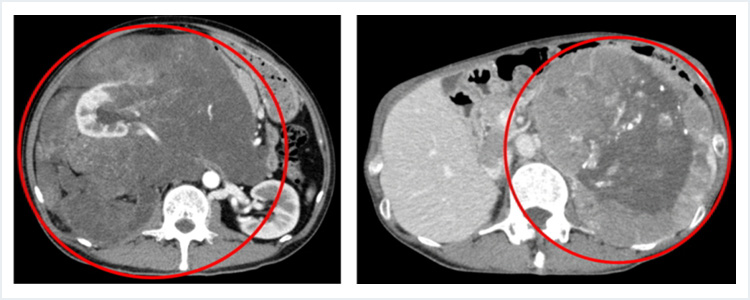

後腹膜の腫瘍

腹部臓器のうち胃や腸などは腹膜という膜に包まれて腹腔内に存在していますが、腹膜に包まれた領域の後ろ側のスペースを後腹膜腔と呼び、腎臓、尿管、膀胱、副腎、大動脈、大静脈などが存在しています。この後腹膜腔に発生した腫瘍を後腹膜腫瘍と称します。そのうち悪性のものとしては副腎癌、傍神経節悪性腫瘍、脂肪肉腫、転移性腫瘍などがあり、外科的切除の対象となることがあります。

当科では後腹膜腫瘍に対しても手術を行っており、過去10年間に87例の後腹膜腫瘍の切除手術を行っております。

腫瘍の内訳は、褐色細胞腫や傍神経節腫瘍、副腎癌、脂肪肉腫などです。臓器移植手術でつちかった技術を応用して腸管や腎臓、血管、筋肉など多臓器の合併切除・再建が必要な腫瘍の切除を行っています。

状況によっては血管外科、泌尿器科、整形外科、形成外科など各診療科と連携して手術を行っています。

また、ホルモンを分泌する褐色細胞腫や傍神経節腫瘍に対しては内分泌内科、麻酔科と連携してホルモン分泌の調整を行いながら切除をしています。

後腹膜腫瘍(左:脂肪肉腫、右:副腎腫瘍)

血管合併切除症例(左:腫瘍(右腎、下大静脈合併切除)、右:下大静脈再建後)